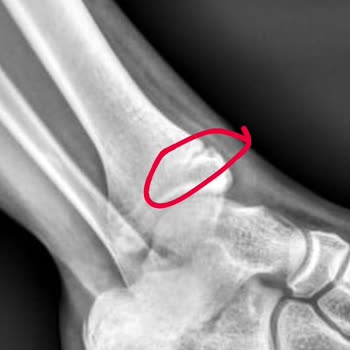

Arnavutköy Devlet Hastanesi'nde cumartesi günü çocuğumun ayağı için acilden giriş yaptık. Röntgen sonrası kırık var deyip alçıya alındı. Pazartesi de ortopediye görünün dendi. Biz de gittik ve doktor bir şeyi yok, 3 gün sonra alçıyı çıkarın dedi. Ben de röntgendeki görüntüde kırık bölgeyi göstererek...